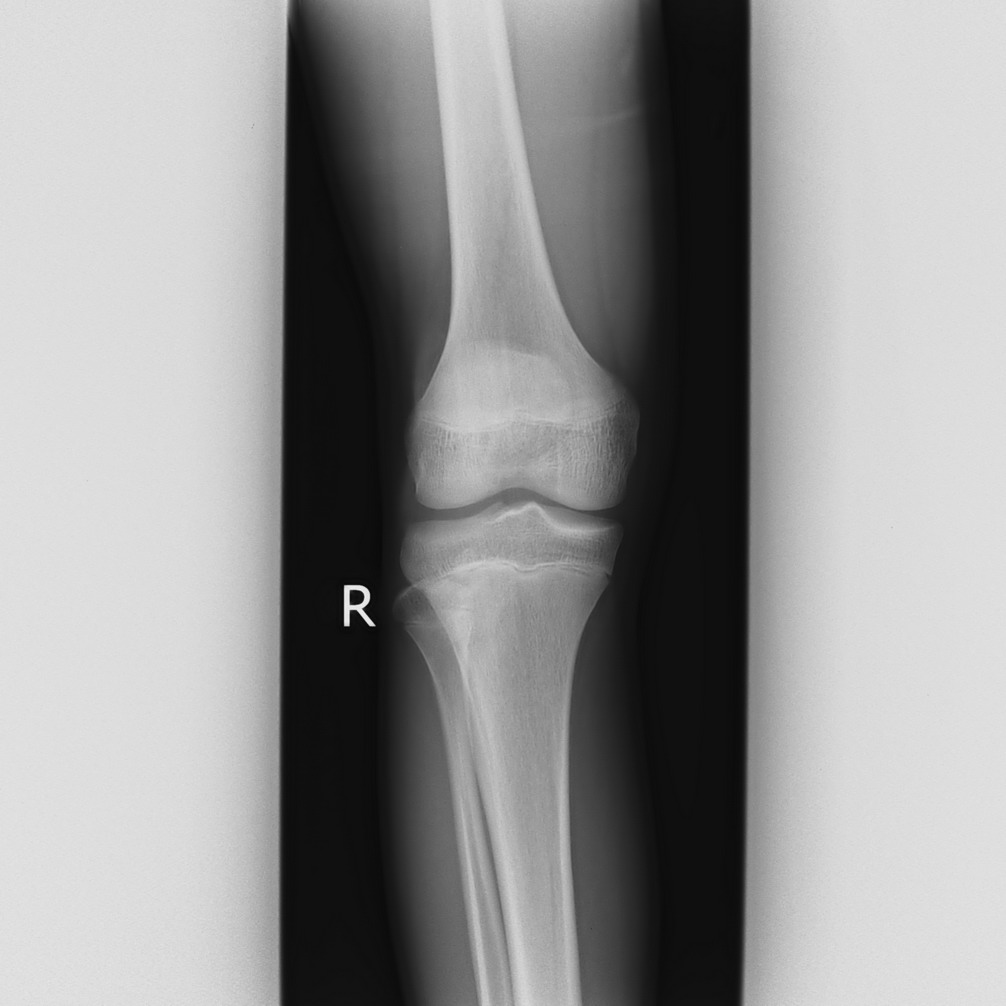

以下是引用qc80012345在2008-5-3 18:26:00的发言:[br]胫前结节缺血性骨软骨炎。

以下是引用宇宙ct在2008-5-3 19:16:00的发言:[br]胫前结节缺血性骨软骨炎